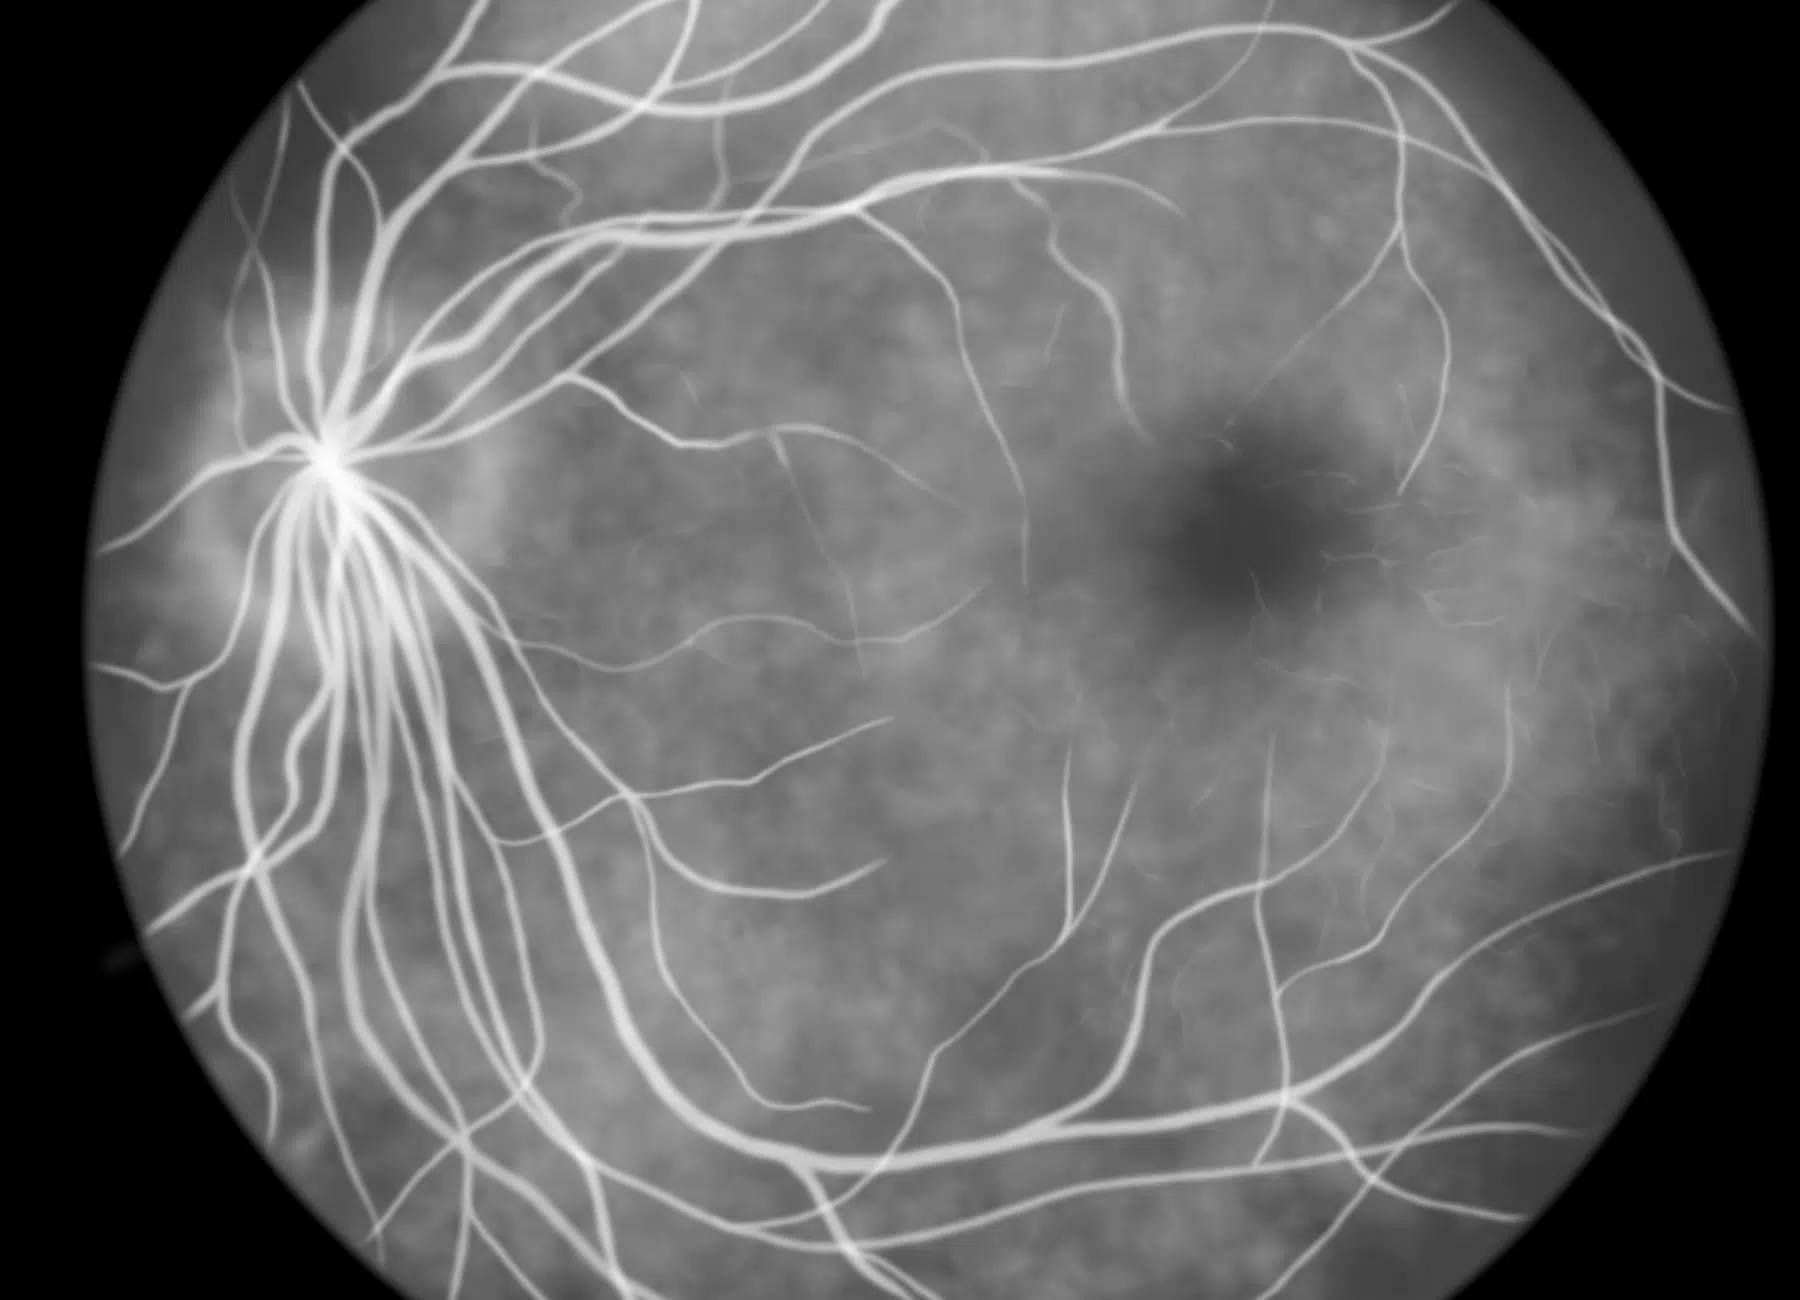

En ophtalmologie, les examens d’angiographie permettent de cartographier la circulation sanguine dans la rétine, essentielle à la détection de nombreuses maladies. Deux approches sont aujourd’hui disponibles : la classique, par injection de produit de contraste, et la moderne, par angio-OCT, plus douce et sans aiguilles.

L’angiographie par injection visualise les vaisseaux de la rétine grâce à l’injection d’un colorant fluorescent dans la circulation sanguine. Elle est utile pour révéler des fuites ou obstructions vasculaires.

À l’inverse, l’angio-OCT n’utilise aucun produit injecté. Elle repose sur une analyse dynamique des flux sanguins à travers une série d’images rapides, détectant les mouvements des globules rouges pour reconstituer le réseau vasculaire rétinien.